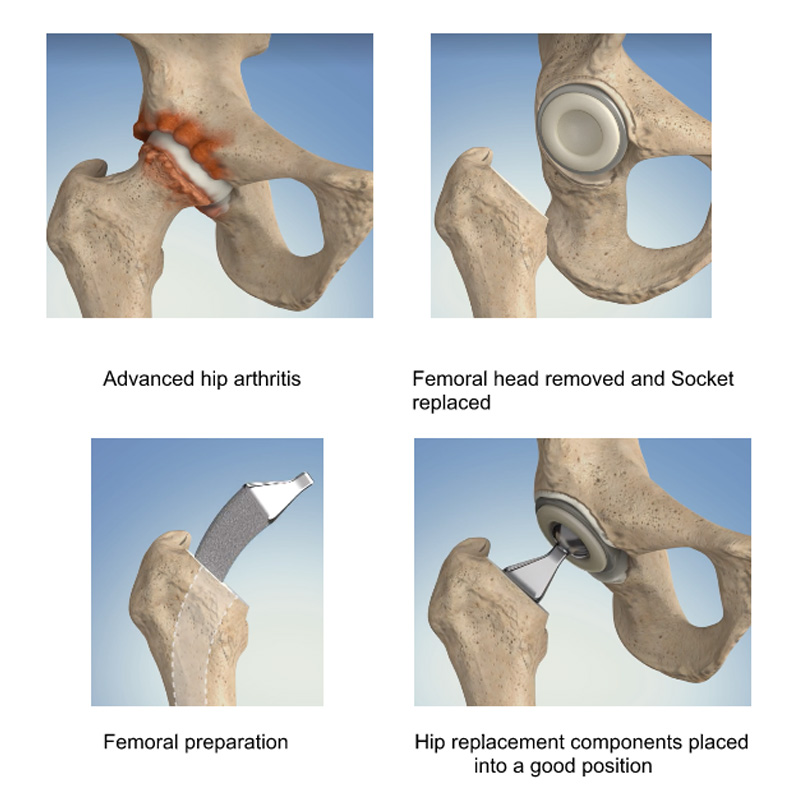

Total Hip Replacement Surgery Anatomical Acetabular Stock Vector

Total Hip Replacement Hip Osteoarthritis

Total Hip Replacement Surgery At UPMC Sports Surgery Clinic